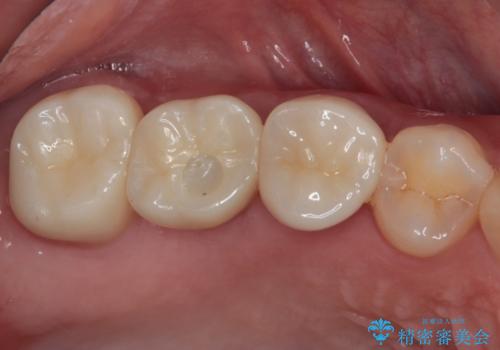

上顎前歯の矮小歯は矯正治療の途中でオールセラミッククラウンを装着し、左右のバランスを整えることとしました。

急速拡大装置の使用により奥歯の咬み合わせが劇的に変わり、その変化を利用して反対咬合を改善することができました。

治療期間中は奥歯が咬み合わず、食事が取りにくいなどの不都合がありましたが、最終的にはきれいに整えることができました。

セラミック治療の注意事項(リスク・副作用など)

- 天然歯を削ります

- 硬い素材は天然歯を傷つけてしまう場合があります

- かみ合わせや歯ぎしりが強すぎる方はセラミックが割れてしまう可能性があります